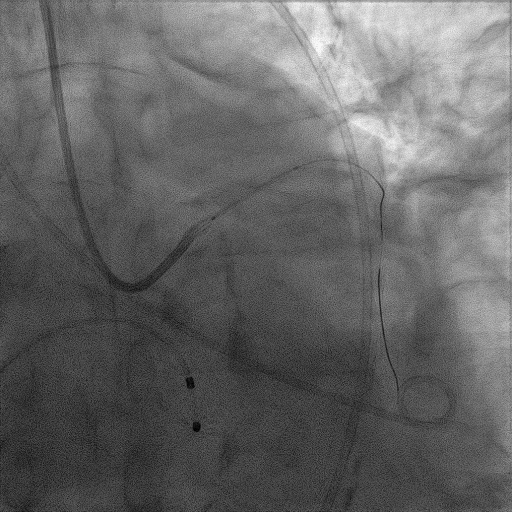

CAG:LAD近中段弥漫钙化,近段80%狭窄,中段90%狭窄,D190%狭窄,中间支近段90%狭窄,右冠近中段弥漫病变,最重狭窄50%。考虑患者胸痛症状可能为冠心病+AS共同作用,以及患者冠脉病变钙化严重,予以旋磨+PCI+TAVR一站式处理。

于中间支植入2.5*18mm支架

1.5mm旋磨头以16万RPM旋磨三次

3.0*15mm球囊后扩张

3.0*15mm球囊预处理LAD近段病变

复查冠脉造影结果满意